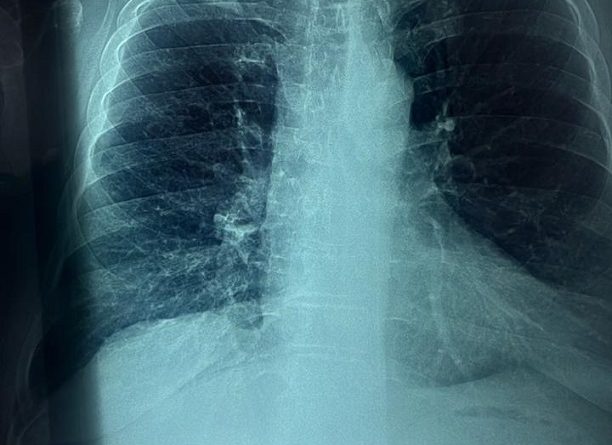

Durante las sesiones, especialistas del ISSSTE le realizaron estudios protocolarios de tórax, los cuales arrojaron presencia de cáncer de pulmón en etapa temprana, por lo que fue intervenido quirúrgicamente en febrero de este año.

“Tenía pocas probabilidades para curarme y el oncólogo -por la posición en la que estaba el tumor- me dijo que se podía eliminar cortando medio pulmón, por lo cual me sometí a la cirugía y gracias a Dios aquí estoy”, expresó.

“Sabemos que el tabaquismo está influido por la nicotina, que es una sustancia muy adictiva, y así como detectamos cáncer de pulmón muy a tiempo en el paciente, vamos a seguir con estos esfuerzos para detectar no solo cáncer, sino más enfermedades, propias del tabaquismo”, concluyó.